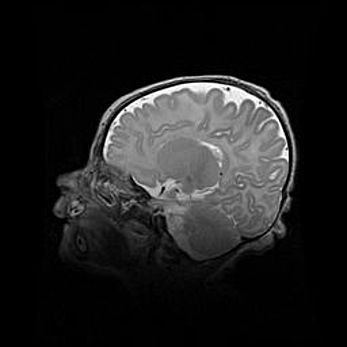

Множественные кисты обоих полушарий головного мозга, наибольшая из них в правой затылочной области. Ассиметричная атрофическая гидроцефалия.

Возраст: 7 месяцев

Вес: 5660 г

Пол: мужской

Окружность головы: 41,5 см

Срок гестации: 28-29 недель

Кисты головного мозга развиваются в результате многоочаговых некрозов вещества мозга и возникают вследствие перенесенной перинатальной инфекции, менингитов, энцефалитов, асфиксии, родовой травмы, расстройств мозгового кровообращения различного генеза. Образованию кист в веществе головного мозга плодов и новорожденных способствуют такие факторы, как высокое содержание в нем воды, недостаточная (или отсутствие) миелинизация и слабая астроглиальная реакция на повреждение.

Кисты могут сочетаться с гидроцефалией и другими поражениями головного мозга.